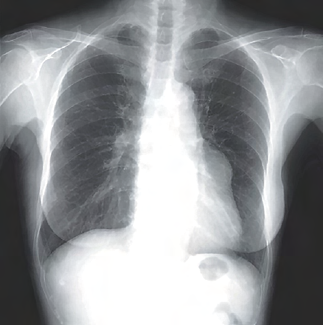

Recent studies indicate that Generative Pre-trained Transformer 4 with Vision (GPT-4V) outperforms human physicians in medical challenge tasks. However, these evaluations primarily focused on the accuracy of multi-choice questions alone. Our study extends the current scope by conducting a comprehensive analysis of GPT-4V's rationales of image comprehension, recall of medical knowledge, and step-by-step multimodal reasoning when solving New England Journal of Medicine (NEJM) Image Challenges - an imaging quiz designed to test the knowledge and diagnostic capabilities of medical professionals. Evaluation results confirmed that GPT-4V outperforms human physicians regarding multi-choice accuracy (88.0% vs. 77.0%, p=0.034). GPT-4V also performs well in cases where physicians incorrectly answer, with over 80% accuracy. However, we discovered that GPT-4V frequently presents flawed rationales in cases where it makes the correct final choices (27.3%), most prominent in image comprehension (21.6%). Regardless of GPT-4V's high accuracy in multi-choice questions, our findings emphasize the necessity for further in-depth evaluations of its rationales before integrating such models into clinical workflows.